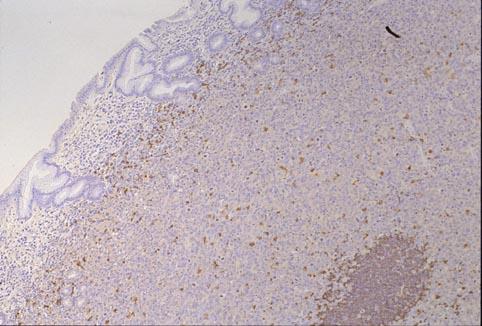

위에 다발병변을 나타낸 성인병 T세포백혈병(ATL)

[Image-ID:2050]

악성 림프계종양 및 혈액계종양/ATL(성인 T세포백혈병)

위(부위)/기타

마이크로

0형(표재형)/IIa형(IIa+IIc)

20~24

sm

유(동시성)